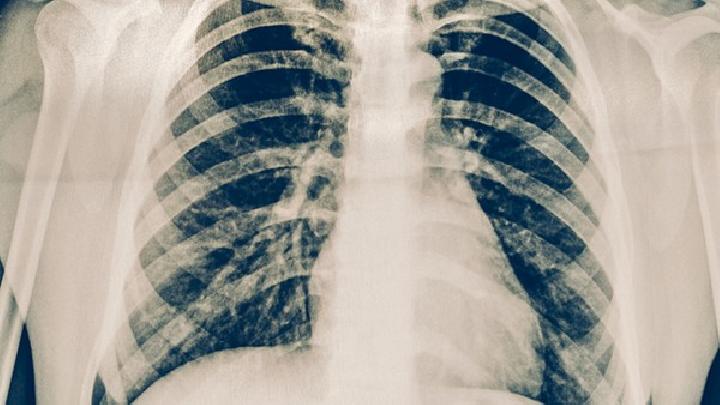

二、X线检查

肺部X线检查不但可早期发现肺结核,而且可对病兆的部位、范围、性质、发展情况和效果作出诊断。